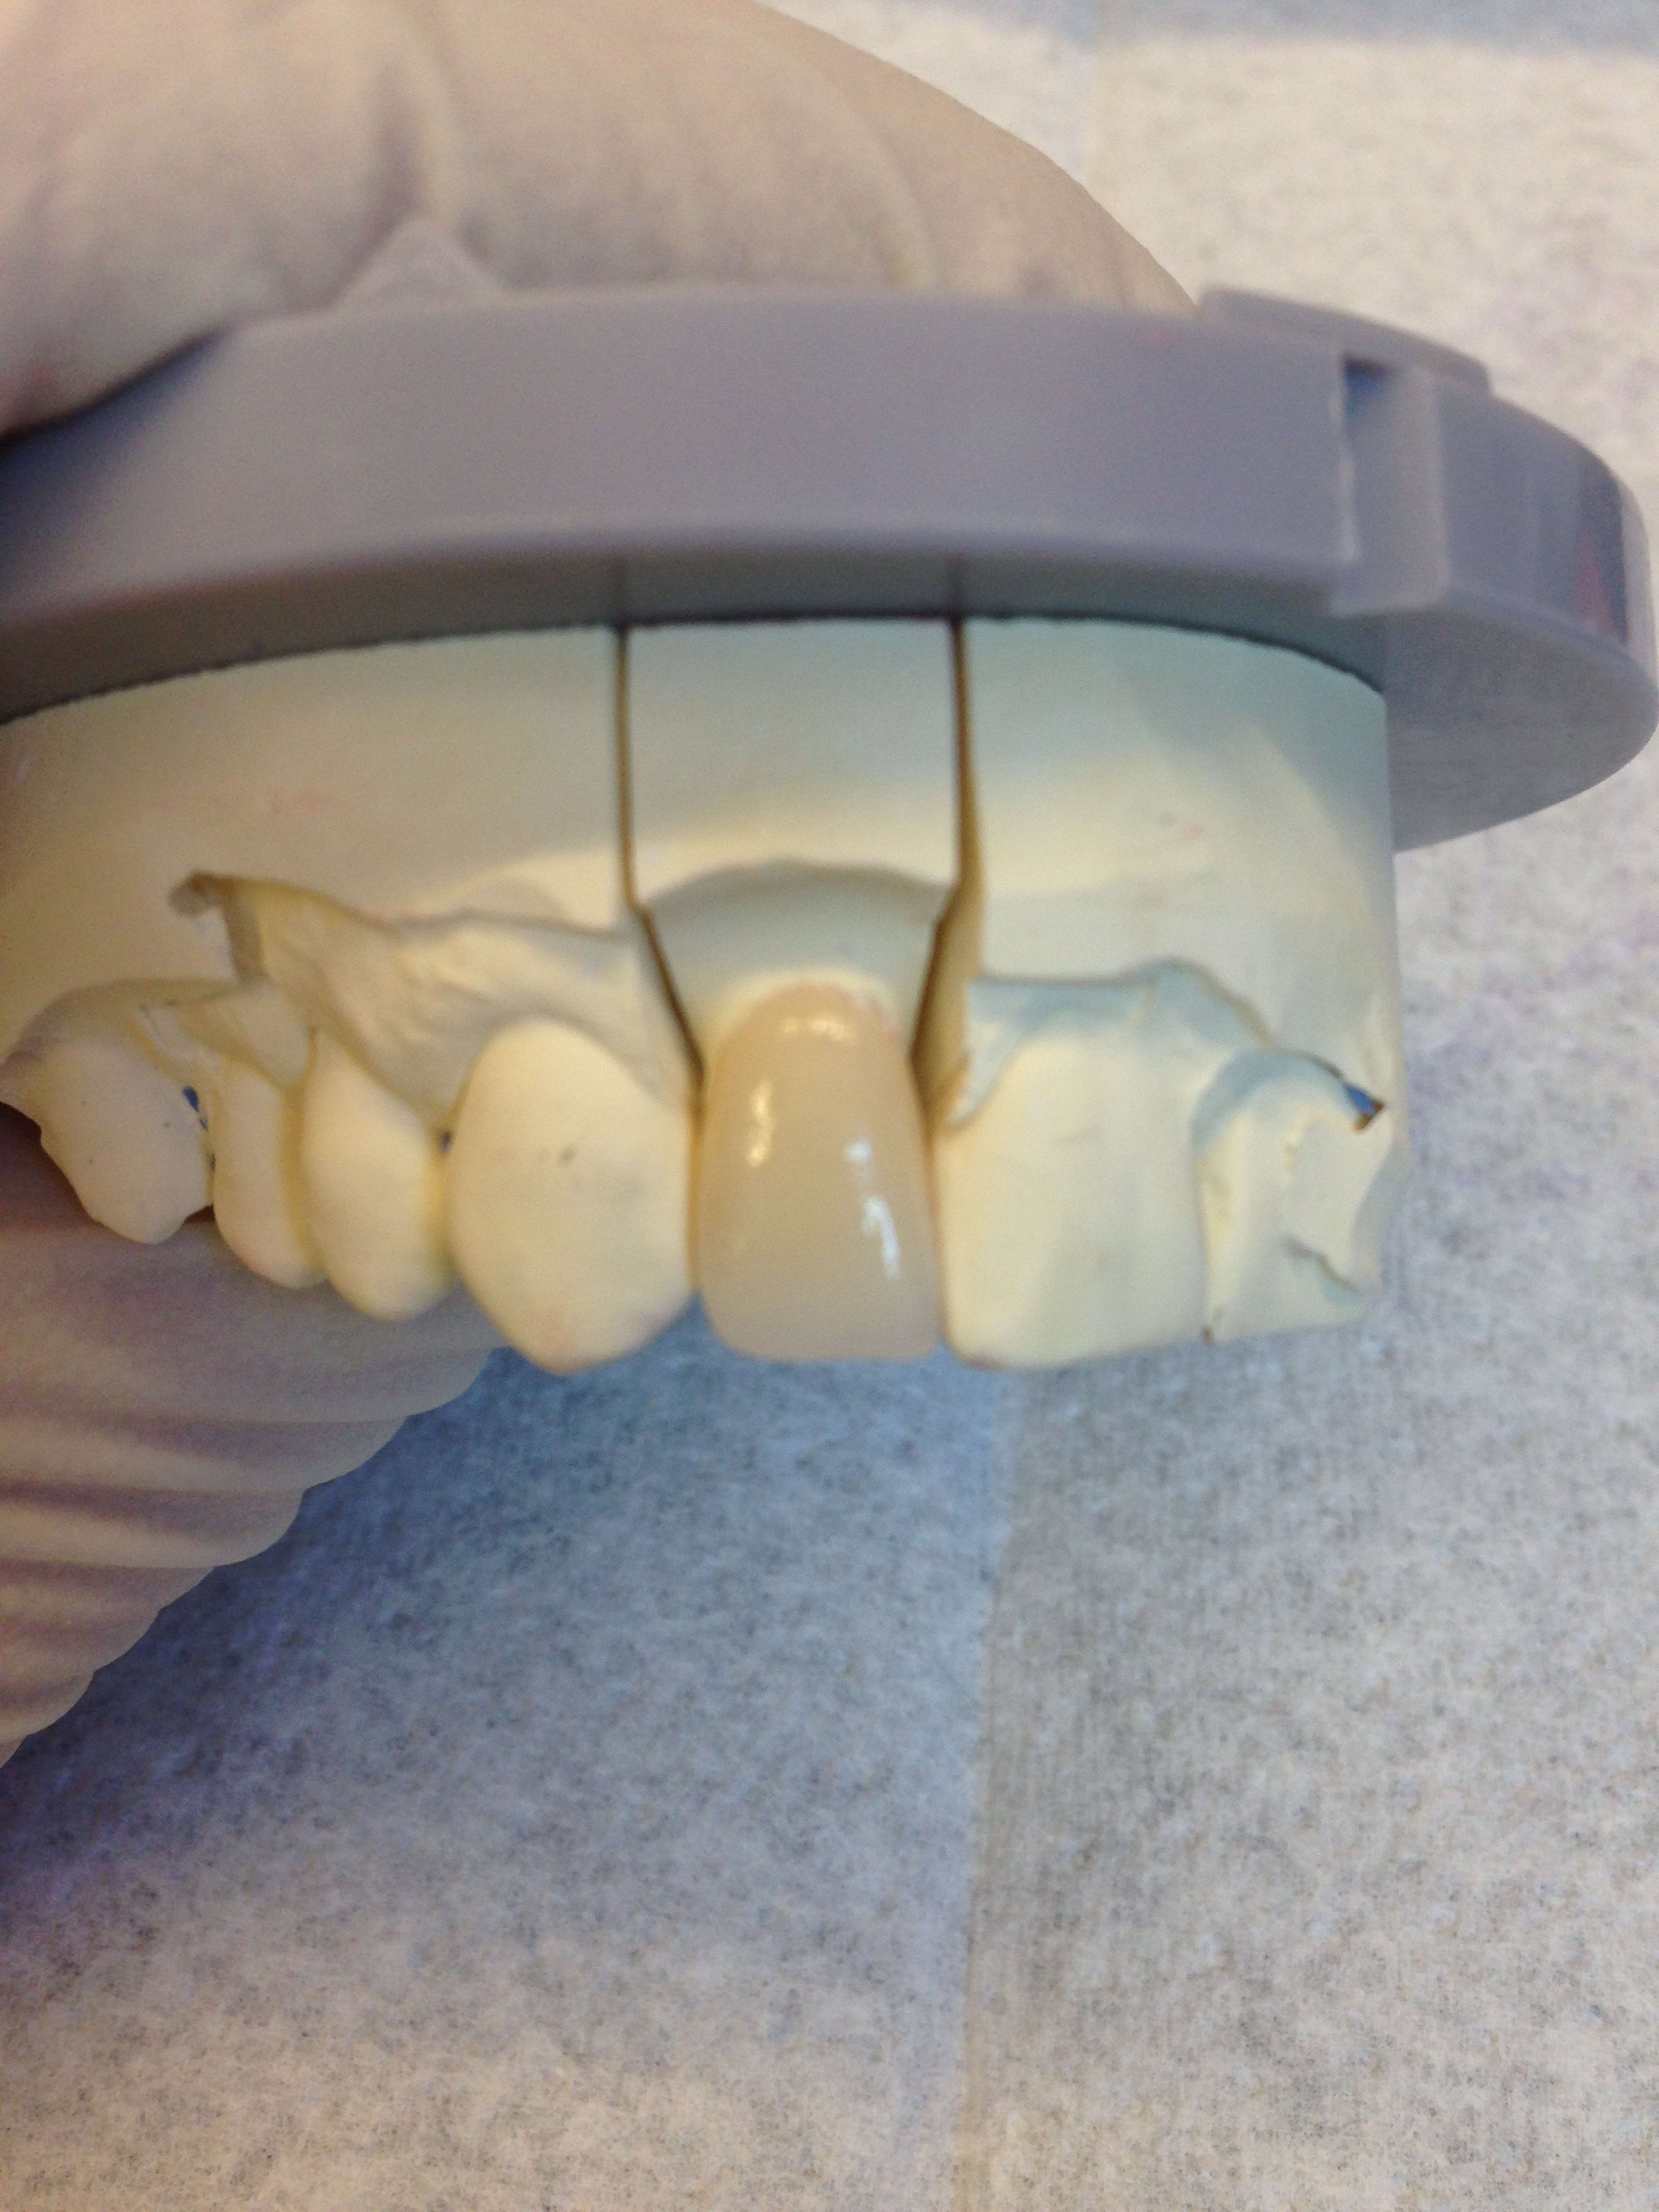

25/02/2017 à 17h43

et celle là c'est pas de la même teinte Vulpi ? On fait moins le malin tout d'un coup. On l'entend plus le Vulpi :)) . On fait profil bas :)

La 12 était comme la 22 , donc correction de la rotation.

Pas la peine de me dire qu'il y a les composites sur les dents d'à coté à refaire. Je commence à vous connaître

Y a la 11 dépulpée qui sera couronnée plus tard (un peu plus jaune la 11)